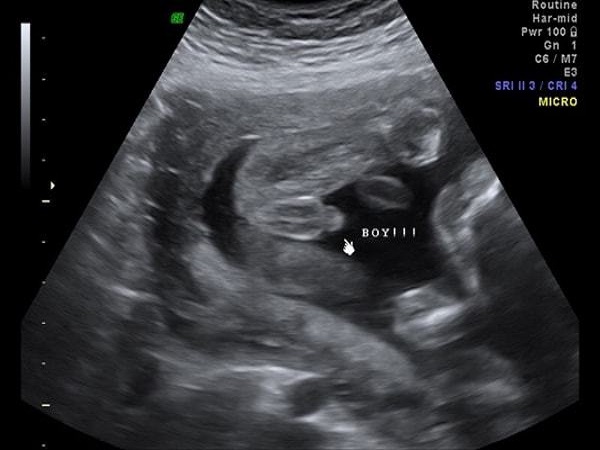

1、看胎儿两腿之间

男孩:如果孕妇怀的是个男宝宝的话,那么彩超图上胎儿两腿之间就应该有凸起,凸起的部分就是男孩的生殖器官,是男性的睾丸;

胎儿两腿之间有凸起就是男孩

女孩:如果怀的是个女孩的话,那么图片上胎儿的两腿之间就不会有凸起,可能会有三条白线,这是女性***的形状,是女孩的典型象征。